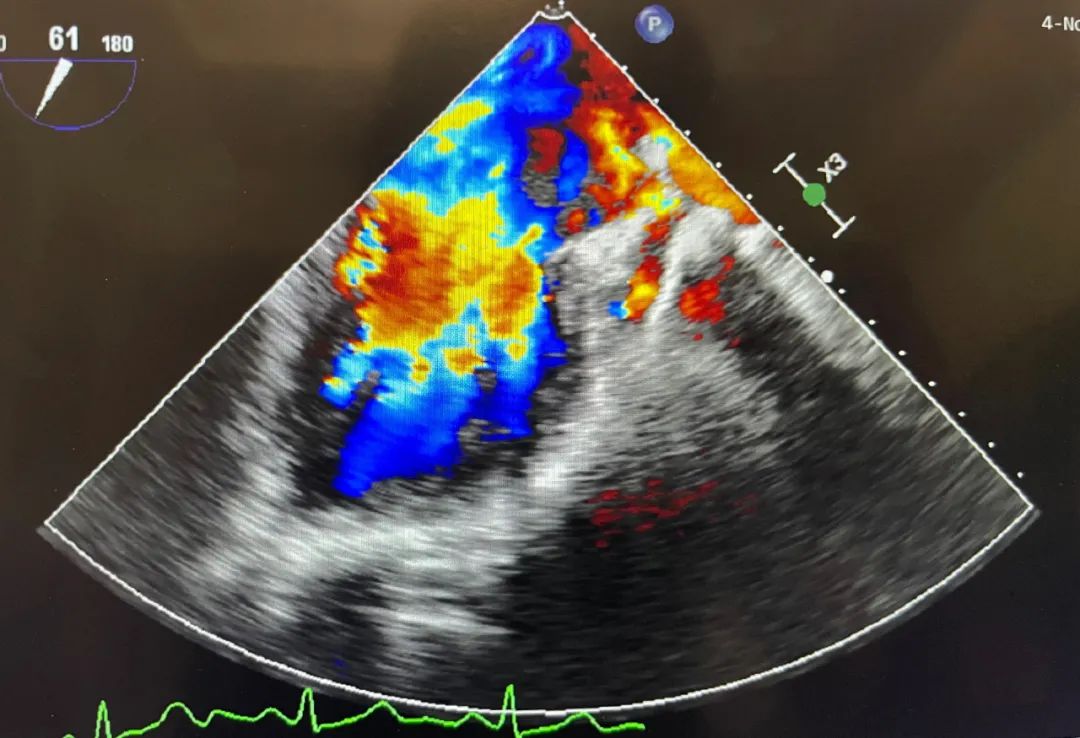

患者为57岁男性,因反复呼吸困难入院,术前心脏彩超显示心房心室明显增大,心肌收缩功能下降,重度二尖瓣反流,二尖瓣后瓣脱垂(P3区)。 患者全麻后,穿刺股静脉,在超声引导下穿刺房间隔,穿刺高度4.0cm,将MitraClip独特的三层双调弯导管和输送系统送入患者左心房,到达二尖瓣A3P3反流处,在经食道超声引导下,通过评估二尖瓣反流位置、抓捕位置、反流程度,精准夹合,成功植入1个二尖瓣夹。

术前